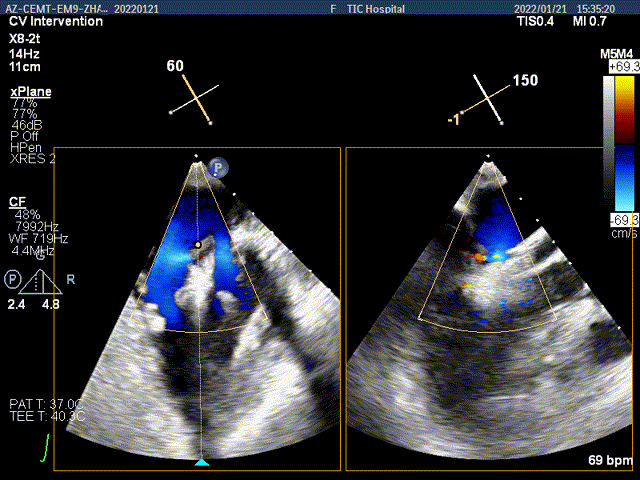

TEE Bicom view:二尖瓣后叶P2区脱垂,宽16.3mm

Color-view:大量反流,主要血流PISA来源于2区

X-plane:下夹子尝试先捕获2区偏内侧瓣叶

该位置夹合后,Color提示内侧区域残余反流较多

打开夹子,并移动到2区偏外侧区域进行夹合

内侧区域残余反流减少